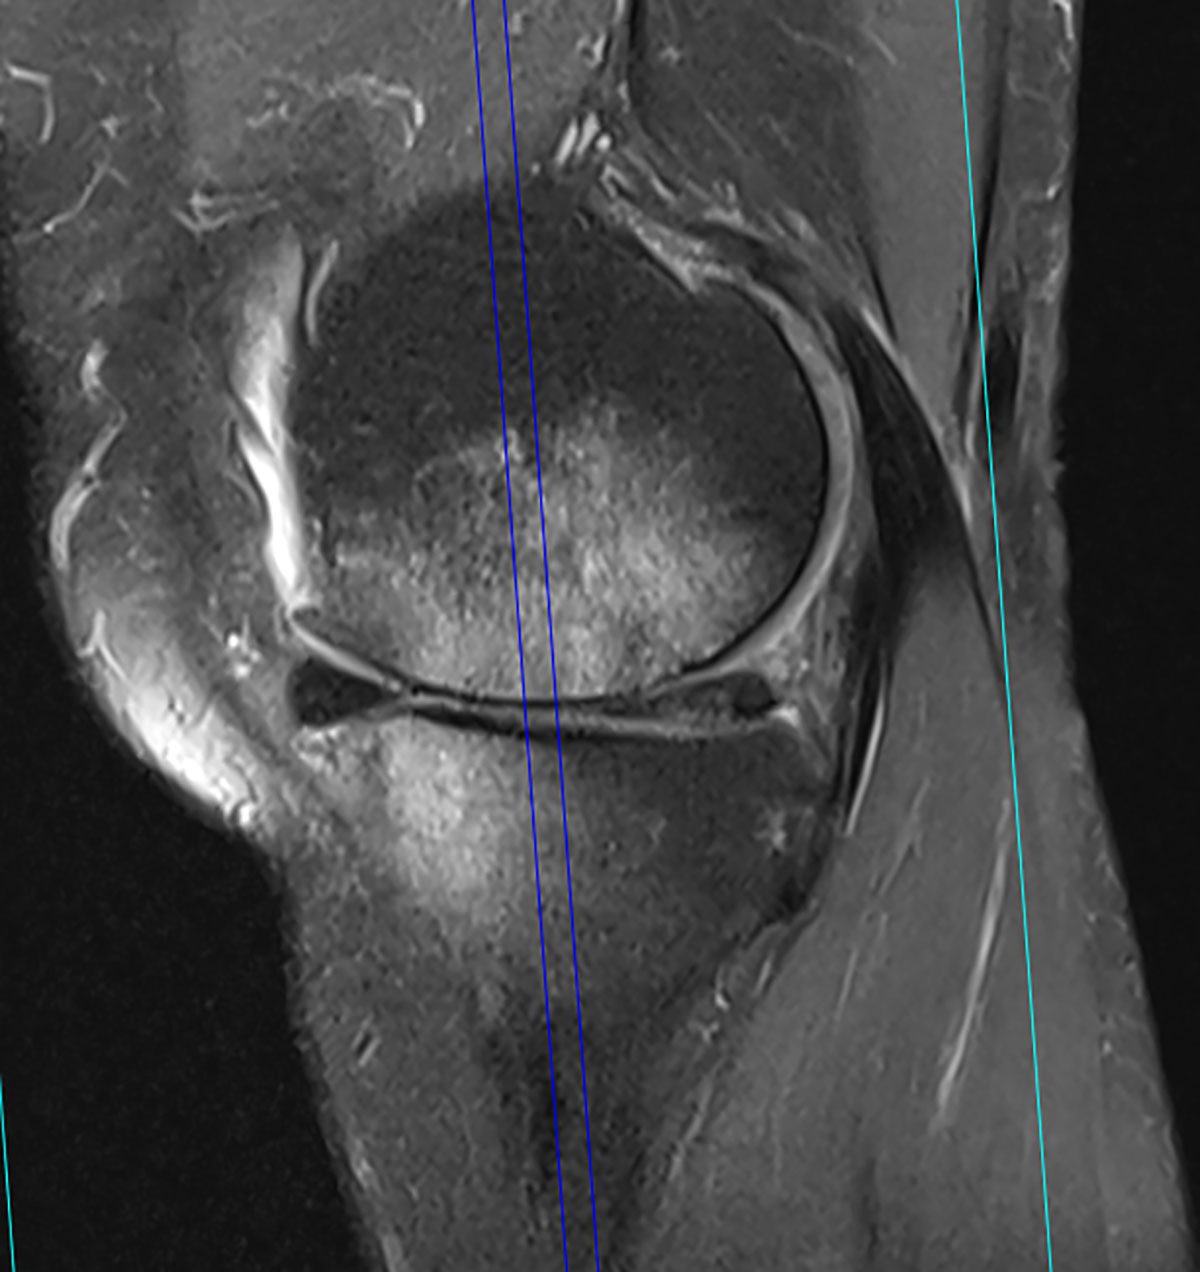

The active 64-year-old [female] patient, whom we had last treated at our practice in the spring of 2020, was already known to us. The patient has pronounced varus osteoarthritis that she developed a few years ago associated with Ahlback’s disease with considerable bone oedema at the time (Fig. 2). She reported that she had been symptom-free for almost two years since our last treatment, and that she could cope well with her everyday living including moderate sporting activities. Now she had once again been exposed to high physical demands while clearing the home of her aged mother, and this had reactivated her symptoms again. She had already had a follow-up MRI performed recently and asked us to quickly start a new course of treatment.

The recent MRI of the right knee joint (06/2022) shows considerably activated varus osteoarthritis, now with increased bone oedema compared with the previous images, effusion associated with irritation, and a small Baker’s cyst.